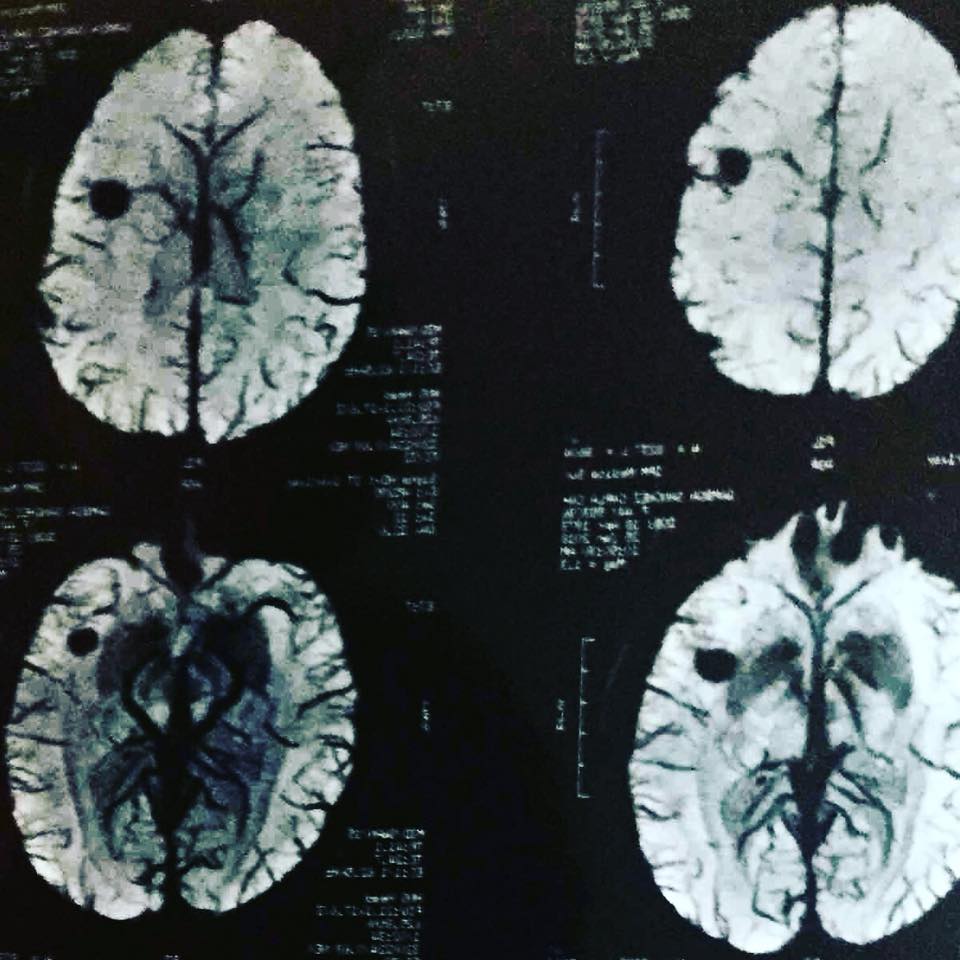

En julio del 2009, tras sufrir una serie de convulsiones, los doctores le realizaron a Carla Gamboa estudios y detectaron Hemangioma Cavernoso en el lóbulo frontal izquierdo. El angioma cavernoso es un grupo de vasos sanguíneos anormales que se encuentran en el cerebro, la médula espinal, y con poca frecuencia, en otras partes del cuerpo. Esta condición se conoce por varios nombres: angioma cavernoso, hemangioma cavernoso, malformación cavernosa cerebral (CCM por sus siglas en inglés) o cavernoma.